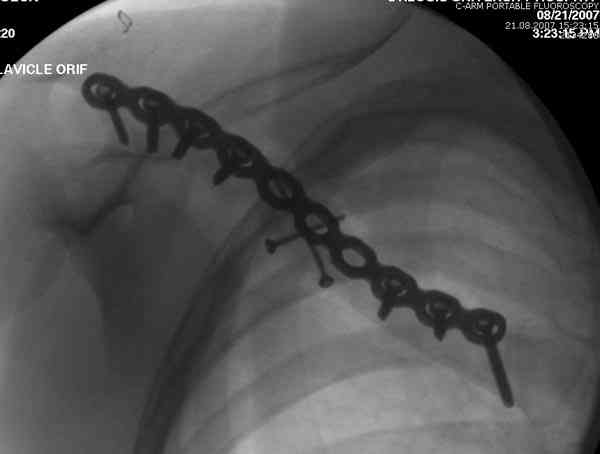

Консервативное лечение, через 8 мес. операция Rockwood pin с костной пластикой в нашем городе другим врачом. После 8 недели падение, гвоздь удален оперирующим хирургом, больная направлена к нам. Фиксация реконструктивной пластиной с трикортикальным графтом, добавлен BMP-2. Для стабилизации фиксацию провели через акромион.

Вот уже два месяца больная также продолжает жаловаться на боли, буквально на днях удалили акромиальную часть пластины с специальной пилой с алмазным покрытием для медицинского металла. До сих пор судьба ложного сустава неизвестна....